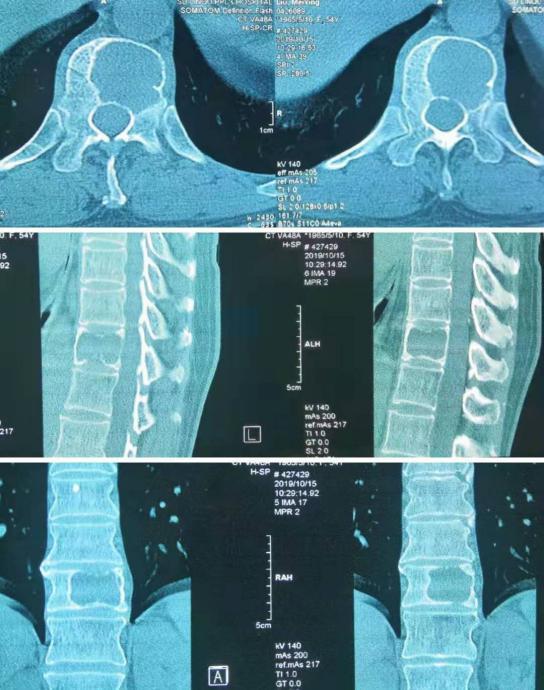

术前CT检查

谭磊副院长仔细阅读患者所有影像学资料后,认为患者胸11椎体侵袭性血管瘤可能性大,胸11椎体被肿瘤破坏近2/3,如果不及时治疗,不恰当的活动可能导致椎体骨折,造成严重脊髓功能障碍而致瘫痪。当机立断,经穿刺活检病理回报考虑为血管瘤,ECT检查未发现其他部位有肿瘤的存在。